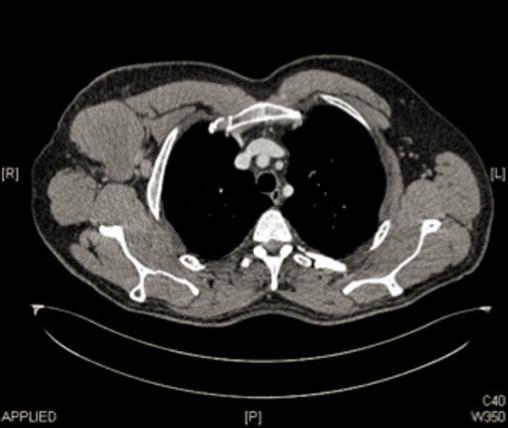

Adénopathie axillaire droite

Lymphome B diffus à grandes cellules